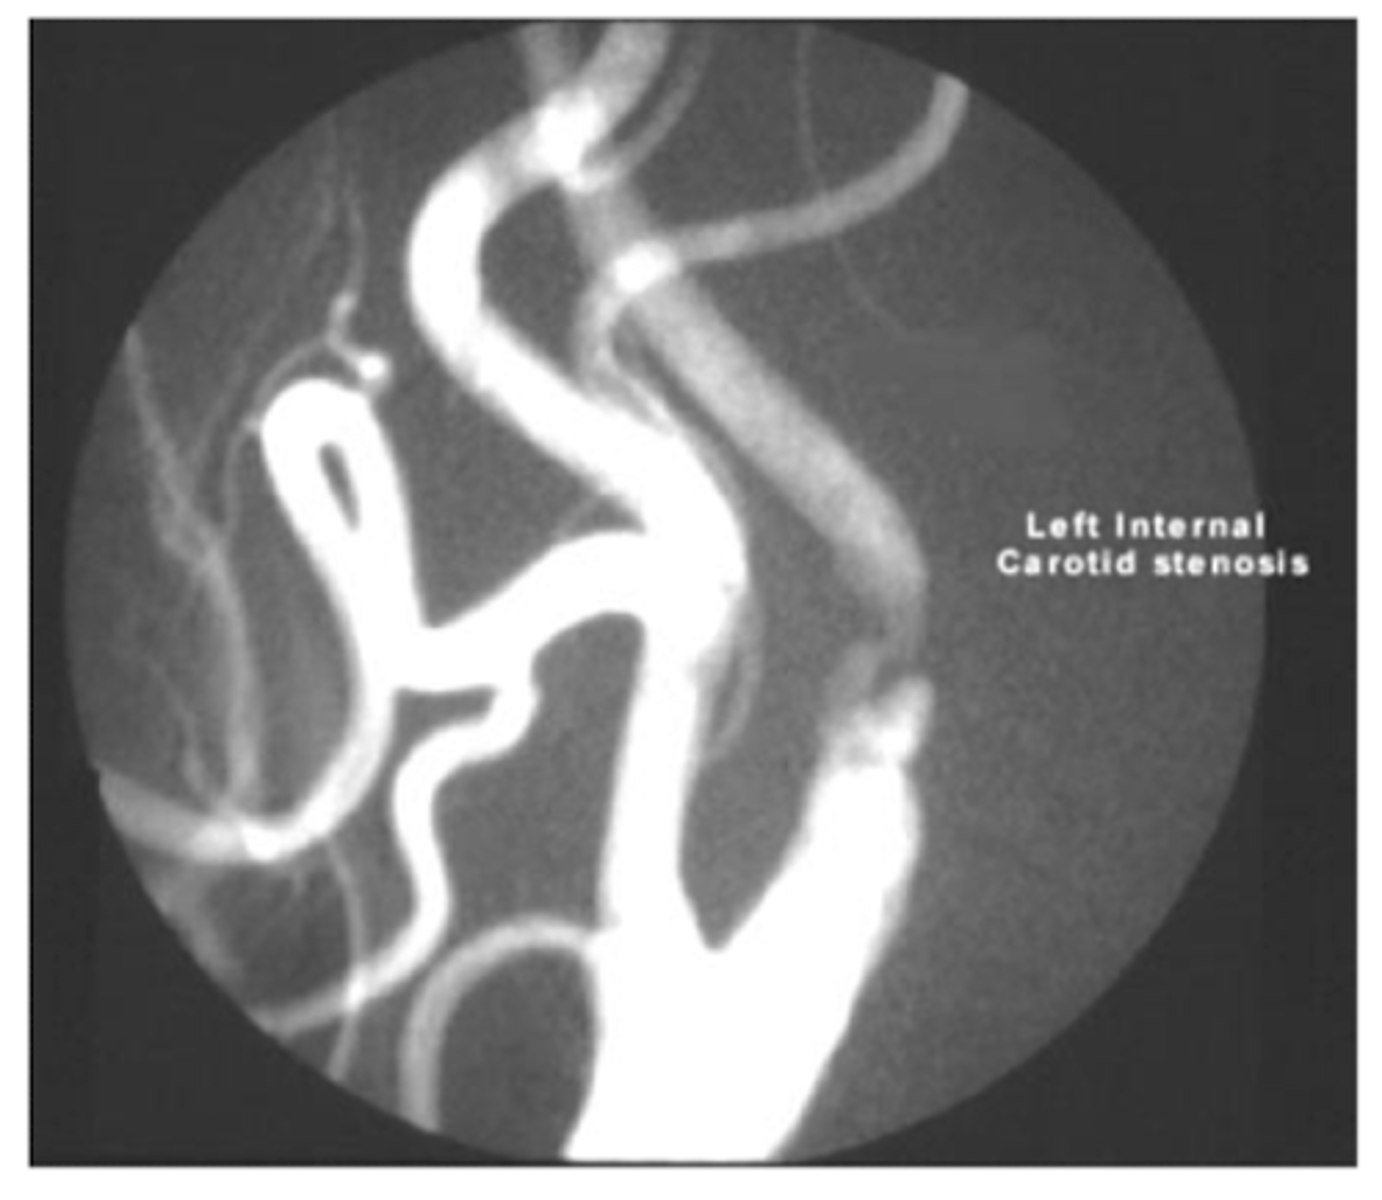

What is the gold standard for evaluating vessels? what is the down side of this testing, and what is used as first line study instead?

contrast angiography - invasive and carries risk of harm to pt

duplex u/s is first line study for vascular dz. can eval anatomy plus direction and magnitude of flow

<p>contrast angiography - invasive and carries risk of harm to pt</p><p>duplex u/s is first line study for vascular dz. can eval anatomy plus direction and magnitude of flow</p>

second line study for peripheral vessels

angiography

<p>angiography</p>